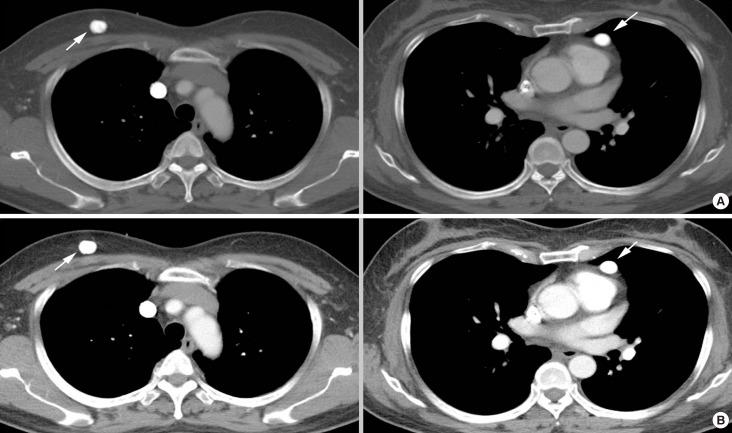

Osteosarcoma most commonly metastasizes to the lung or the skeleton, and metastatic osteosarcoma to the breast is very rare, with only a few cases reported. Due to its rarity, little has been reported about its imaging features. In this report, we represent a 58-year-old woman with metastatic osteosarcoma to the right breast from a tibial osteosarcoma. The imaging features of the metastatic osteosarcoma to the breast by using dedicated breast imaging modalities are described. Although rare, metastatic osteosarcoma to the breast should be considered when dense calcified masses with suspicious features are seen on breast imaging in patients with a history of osteosarcoma.

摘要

骨肉瘤最常转移至肺或骨骼,而骨肉瘤转移至乳腺极为罕见,仅有少数病例报道。由于其罕见性,关于其影像学特征的报道很少。在本报告中,我们介绍了一名58岁女性,其右乳腺的骨肉瘤转移灶来自胫骨骨肉瘤。描述了使用专用乳腺成像模式时乳腺转移性骨肉瘤的影像学特征。尽管罕见,但对于有骨肉瘤病史的患者,当乳腺成像中发现具有可疑特征的致密钙化肿块时,应考虑骨肉瘤转移至乳腺的情况。